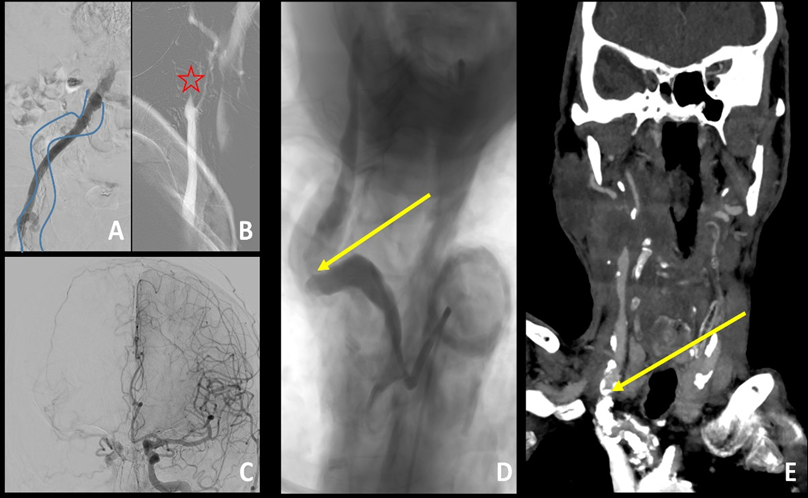

An 81-year-old man presented with left-sided hemiparesis and dysarthria upon awakening, consistent with a wake-up stroke. He had a history of coronary artery disease, previous minor stroke due to right carotid artery stenosis managed with endarterectomy and chronic peripheral vascular disease treated with an aortobifemoral bypass. Computed tomography (CT) showed no early signs of ischemia (Figure 1A), but demonstrated occlusion of the right internal carotid artery (ICA) along with distal occlusion of the middle cerebral artery (MCA) (Figure 1B). CT perfusion imaging revealed a large ischemic penumbra, estimated at 136 mL (Figure 1C). Diagnostic angiography was performed via puncture of the right aortofemoral graft (Figure 2A), confirming right ICA occlusion with poor collateral flow from the contralateral carotid circulation (Figures 2B-C). Severe calcified stenosis at the origin of the right common carotid artery (CCA) precluded mechanical thrombectomy (MT) via both femoral and radial access routes (Figures 2D-E).

Under general anesthesia and ultrasound guidance, direct puncture of the right CCA was performed approximately 2 cm above the clavicle. A 0.025” wire was advanced toward the external carotid artery. After needle removal, a 6F thin-wall sheath (Glidesheath Slender; Terumo Medical, Somerset, NJ, USA) was inserted into the right CCA. A 0.014” guidewire was then placed into the right ICA, followed by balloon angioplasty using a 4×20 mm catheter.

Figure 2: Diagnostic angiography was performed via puncture of the right aortofemoral graft (native femoral artery was underlined by blue curved lines; A). It confirmed occlusion of right ICA (red star; B) with poor collateral circulation from contralateral carotid artery (C). Moreover severe calcific stenosis at origin of CCA (yellow arrow; D-E) was identified.